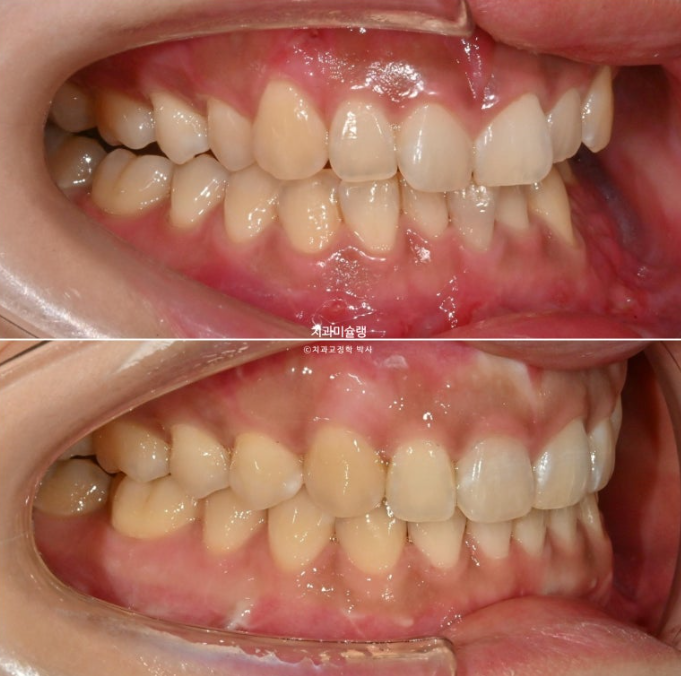

선수술 후 한달간의 회복기를 거쳐 25년 1월 본원에 내원했을 때의 교합 상태입니다.

25.01

앞니 두 개는 나비치아 돌출이며

어금니 교합이 떠있습니다.

앞니에 배열이 삐뚤합니다.

중심선은 정확히 맞으며

어금니 교합은 물샐틈 없는 1급 교합관계를 보입니다.

25.02~25.10